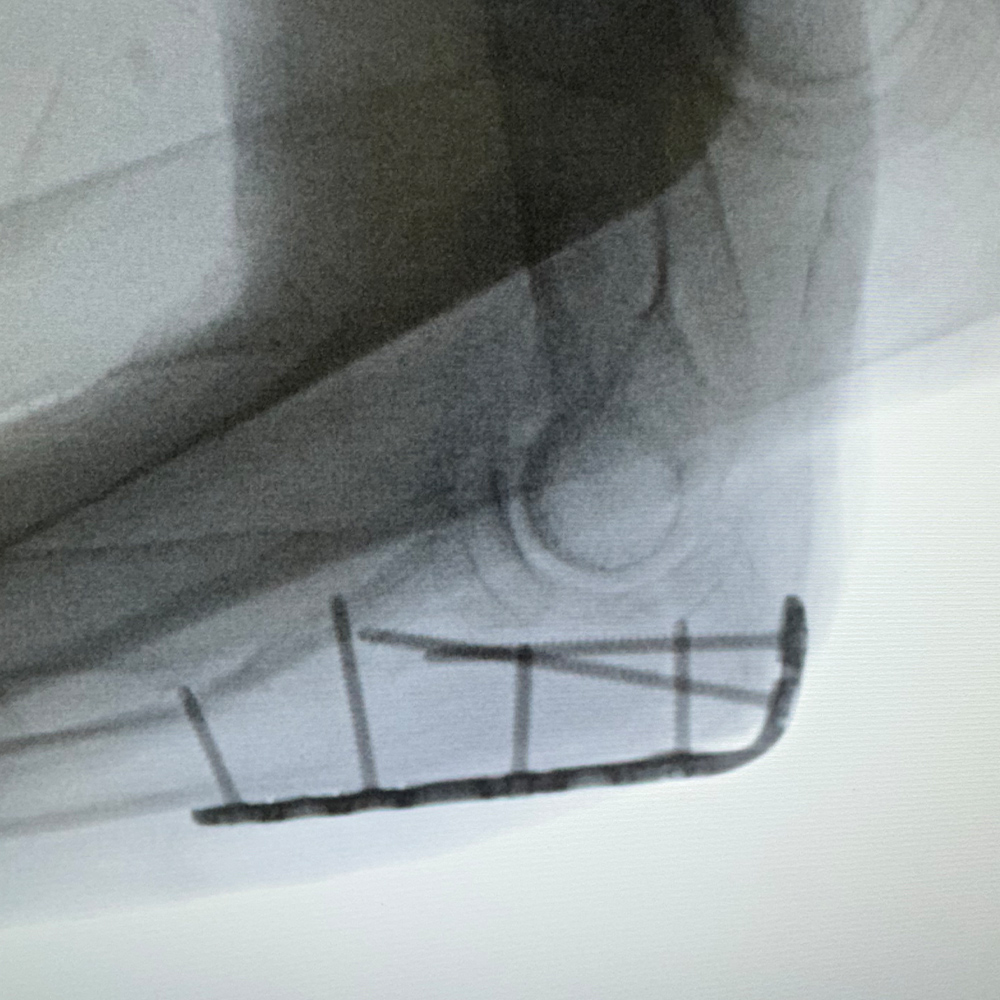

Distal Radius

PLATING SYSTEM 2.0

- Titanium low profile construct

- 45° Polyaxial locking

- Strong & consistent locking mechanism

- Option to use both 2.0mm screws and 1.8mm pegs distally

- Ability to choose between 7 or 8 screw/peg holes distally to reduce screw cutout and optimize fixation

- Completely flush with no sharp edges

- Locking caps allow all screws to compress the plate to bone before locking

- Locking caps improve fatigue properties and prevent screw backout

- 360° Rotation allows for proximal/distal translation as well as medial/lateral translation and all other oblique angles